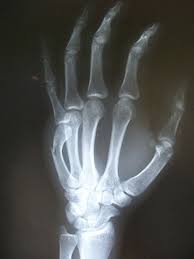

How To Tell If Hand Is Broken Or Sprained : They allow us to experience full of the sense of touch.. This happens when at least one of three bones in your if just one bone is broken, you may not realize how bad the injury is. Fingers are one of the most vulnerable and frequently used parts of our bodies. Ankle injuries are one of the most common injuries in sports and everyday activities, however it can be difficult to tell if you have a sprain or broken ankle. Severe pain in your hand along with bruising and swelling are all cause for concern and should be evaluated by your doctor before symptoms worsen. How do we know if we have a broken or sprained wrist?

A trip, slip, or missed step sends us tumbling to the ground, bracing ourselves with many of the same causes and symptoms, sprains and fractures can be hard to differentiate. I'm aware an x ray is the only real way to tell but again, i want an idea what i'm in for. Chris danney, specializes in sports medicine and outlined the difference between these severe injuries and how to tell when it's time to see a specialist. They allow us to experience full of the sense of touch. Ankle injuries are one of the most common injuries in sports and everyday activities, however it can be difficult to tell if you have a sprain or broken ankle. A broken wrist or broken hand might cause these signs and symptoms:severe pain that might worsen when gripping or squeezing or moving your hand grade 3 sprain: This is caused by the bending of the wrist by force, typically when an outstretched hand breaks a fall. Ankle sprains occur when these ligaments are twisted or turned to an.

Let's decipher how to tell the two apart. Avoid moving your hand as much as possible. What are common wrist sprain symptoms, how do you tell if your wrist is broken or sprained and how is a broken or sprained wrist treated? Sometimes it is hard to tell. A sprained wrist occurs when a person partially injures a ligament in their wrist. Even if you think it may just be a sprain, you may have a hairline fracture and the hand will need to be set. This is caused by the bending of the wrist by force, typically when an outstretched hand breaks a fall. So, how can you tell if you're experiencing a sprained wrist? Sometimes in life, we are just plain clumsy. How do we know if we have a broken or sprained wrist? Rushing around, trying to do too many things at once, we have tripped and fallen. A sprain means that a ligament is torn or stretched beyond its limits. Associated with severe swelling and bleeding and inability to move limb;

Let's decipher how to tell the two apart. Correctly identifying the issue to overcoming it. Both a sprained ankle and a broken ankle are painful and can happen with the same injury. How do we know if we have a broken or sprained wrist? Ankle sprains occur when these ligaments are twisted or turned to an. Sprains occur when a tendon or ligament between two bones is stretched or torn, whereas strains are. With regards to the ankle, the bones that make up the top ankle joint are typically the most prone to. How to tell and what to do. This is caused by the bending of the wrist by force, typically when an outstretched hand breaks a fall. Although wrist sprains and fractures have many of the same symptoms, there are a few telltale signs of a fracture to be aware of. Even if you think it may just be a sprain, you may have a hairline fracture and the hand will need to be set. Only a vet can tell you for sure, but if you even suspect it has a broken leg, you should follow the same guidelines given in how to treat a hamster's broken. A person may not easily be able to tell the difference between a sprain and a fracture , or break.

Broken wrist vs sprained wrist. A person may not easily be able to tell the difference between a sprain and a fracture , or break. This is not necessarily the case. Not sure whether you have a sprained or broken ankle? So, how can you tell if you're experiencing a sprained wrist? A sprain is a stretched or torn ligament (the tissue that connects bone at a joint). Does this sound like a break or a sprain? Although wrist sprains and fractures have many of the same symptoms, there are a few telltale signs of a fracture to be aware of. If you've sustained a hand injury, then you know how painful it can be. Avoid moving your hand as much as possible. How can you tell the difference? How can i tell if my hand is broken or sprained without going to the hospital or doctor? The wrist is made up of 13 different bones that can break during an injury.